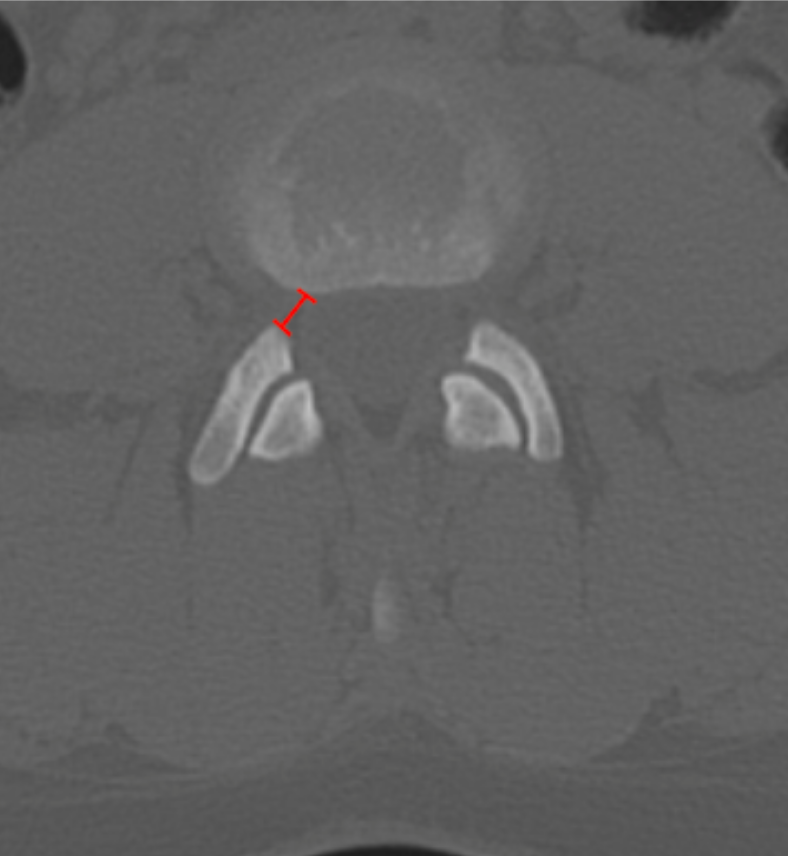

Lumbar lateral recess depth (or width) quantifies the available osseous space for the traversing nerve root between the pedicle medially and the superior articular facet laterally/posteriorly. Narrowing of this region is a common cause of radicular pain and may occur even when central canal dimensions appear normal.

This CT-based measurement reflects bony encroachment from facet hypertrophy, osteophytes, or congenital narrowing.

• Scroll to the axial CT slice at the pedicle level where the lateral recess is best visualized.

• Draw a straight line between these two points following the course of the traversing nerve root.

• Measure this distance in millimeters (mm) — this is the lateral recess depth / width.

3) Normal vs. Pathologic Ranges

• Normal: ≥ 5 mm

• Relative stenosis: 3 - 5 mm

• Severe lateral recess stenosis: < 3 mm

• Critical stenosis: Root obliteration

Values < 3 mm strongly correlate with symptomatic nerve root compression.